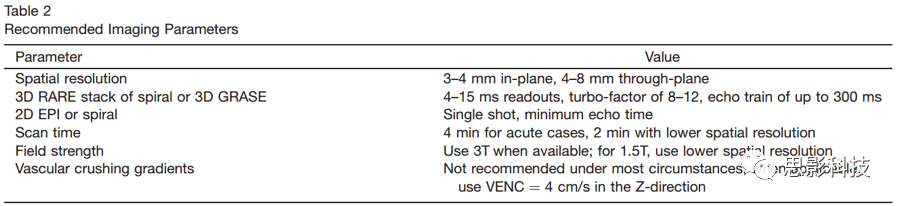

三维分割读取

对于3D读出,分配给图像采集的每个TR内的时间通常比多个2D切片的时间短,从而可以更有效地利用时间。3D RARE的螺旋叠加和3D GRASE表现类似,这两个在特定系统上会优化得更好。需要注意的是,快速自旋回波螺旋式K空间填充叠加方式在k空间中心提供了自然的过采样,这可以改善运动不敏感,但也有可能由于共振偏移导致平面内模糊。相比之下,GRASE通常不会过量使用k空间,而三维GRASE中的共振偏移会导致平面内失真。对于多次成像,应按顺序获取给定图像的标签和控制条件,以实现最准确的标签与控制之间的差值计算。用户还应注意,回波之间与T2相关的信号调制可能会导致平面模糊。如果图像重建软件是供应商提供的,则建议您咨询其用于纠正图像模糊和失真的方法,以便可以适当地解释图像。用于校正的方法和参数应在报告ASL数据的文章中需要加以说明,因为它们可能会对站点之间数据的比较产生重大影响。有关推荐的成像参数,请参见表2。

单次扫描的读出

第二选择是2D单次成像方法,其可有效地应用于ASL。 EPI和螺旋方法已被广泛使用,而单次RARE和平衡SSFP也是可行的,但是不那么常见,并且这种读出方法针对ASL的测试还不够深入。对于ASL,EPI和Spiral的性能,彼此相似,但差异很小。螺旋可以缩短回波时间(TE),以减少T2 / T2 *的权重,但会产生与共振无关的模糊。 EPI具有更长的最小回波时间,但在共振偏移的情况下会表现出失真而非模糊。至于3D成像,建议在特定系统上更好地优化这两种方法中的任何一种。通常,对于单次2D读数,建议使用升序切片顺序。单次成像方法的优点之一是,它们不受运动伪影的影响。对于2D成像,背景抑制技术仅对一个或几个切片而言是最佳的。尽管这通常是一个缺点,但残留的静态组织信号可能会以两种方式使用。首先,可以使用幅度图像重建,它比复杂的重建和线圈组合要简单。第二,残留信号可以在标签与控制相减之前用于图像配准。尽管背景抑制在2D单次成像中的影响远不如3D成像中的剧烈(图6),但可以看到信号波动显著降低,尤其是在患者运动明显的情况下,建议使用背景抑制。有关其他推荐的成像参数,请参见表2。

扫描时间

由于ASL信号较小,ASL依赖于平均计算来获得足够的信噪比。增加平均值会增加信噪比,降低运动伪影的影响,并为数据过滤提供更多的机会。使用此处描述的默认参数时,总扫描时间为4分钟,并可在实验被试中产生良好的图像质量。对于急性环境中的快速成像,低至2分钟的扫描时间即可提供可解释的数据,在这些情况下,建议降低空间分辨率以补偿信噪比损失。